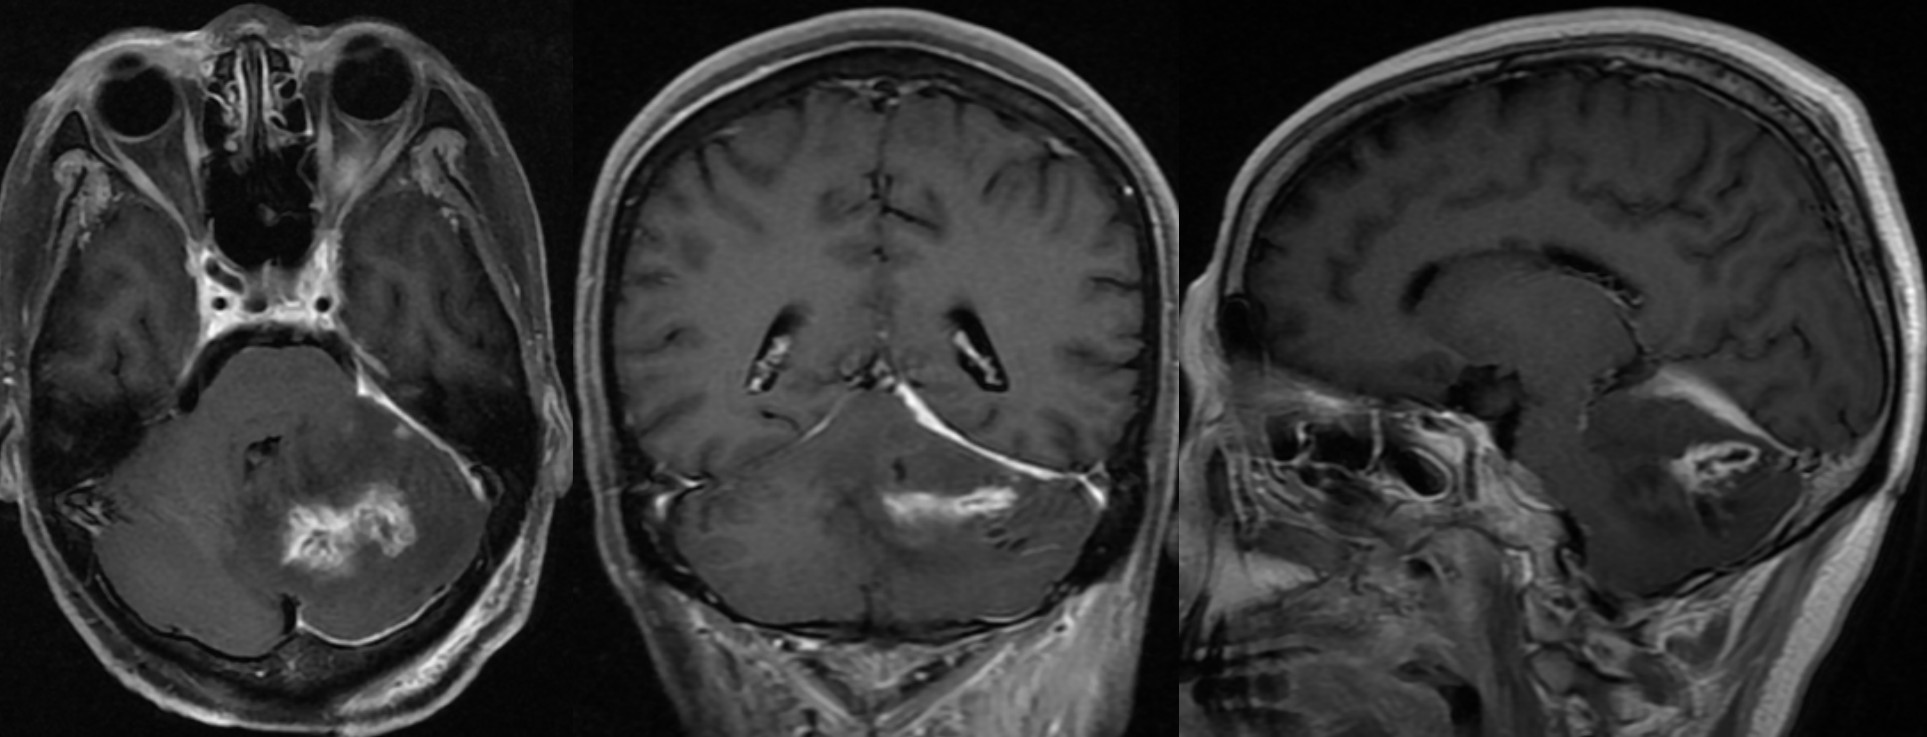

复查头颅MRI提示小脑幕区脓腔缩小,左侧小脑半球脓腔扩大,周围水肿较重,占位效应明显,脑干明显受压。

3月23日复查头颅MRI提示脓腔基本消失,仍可见脓肿壁,占位效应减轻。